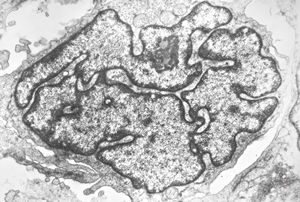

F, 37y. | mycosis fungoides … cerebriform nucleus of Sézary cell